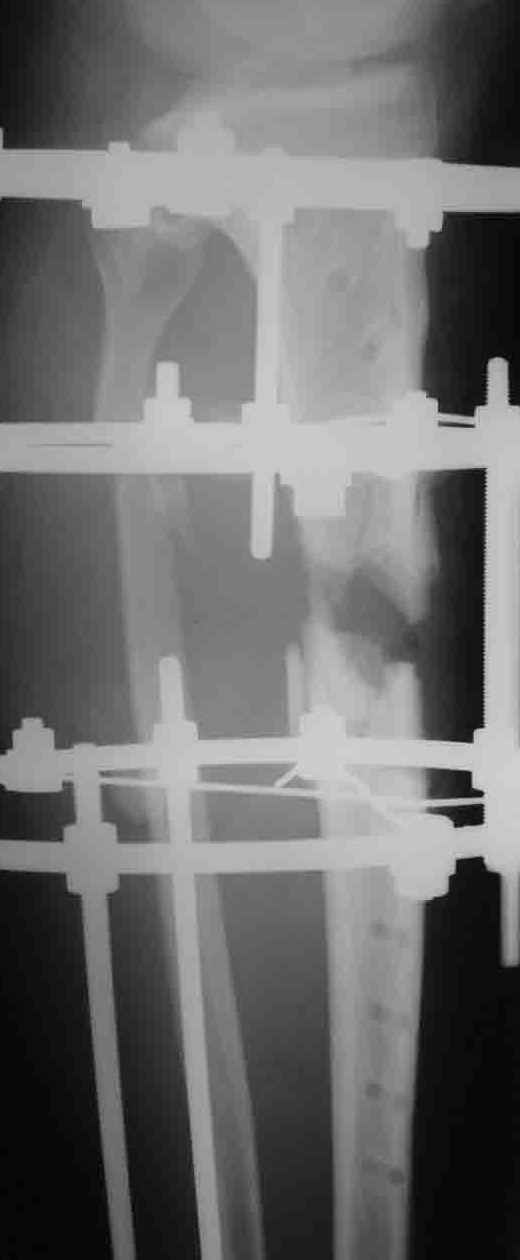

Что-то рано сломалась пластина - в чем видите причину?

Уважаемый Алексей, глядя на Р-граммы левой голени фиксированной пластиной создается впечатление, что имеется дефект б/берцовой кости. Учитывая это при ЧКО необходимо выполнить костную пластику дефекта. В противном случае кость даже после консолидиции останется слабой, что приведет к повторному перелому. Мне кажется, что в данном случае предпочтителен ЗИО б\берцовой кости с рассверливанием костномозгового канала и блокированием, т.к. при ЗИО активизируются процессы регенерации за счет гематомы в области перелома, что приводит к образованию параоссальной костной мозоли. Плюс к этому в кости будет находится прочный фиксатор, который очень редко ломается и не беспокоит пациента.

Перелом пластины наступил, по нашему мнению, вследствии проведенного нестабильного остеосинтеза (необходимо было выполнить накостный остеосинтез с костной аутопластикой). Возможно проведение данной операции и в настоящее время, то есть при удалении сломанной пластины вновь выполнить стабильный накостный остеосинтез с костной аутопластикой.

Причина перелома - на мой взгляд - неадекватная репозиция. Сегмент удлинен, об этом говорит диастаз между отломками малоберцовой кости. Отсюда и впечатление "дефекта". Он есть, но вторичен.